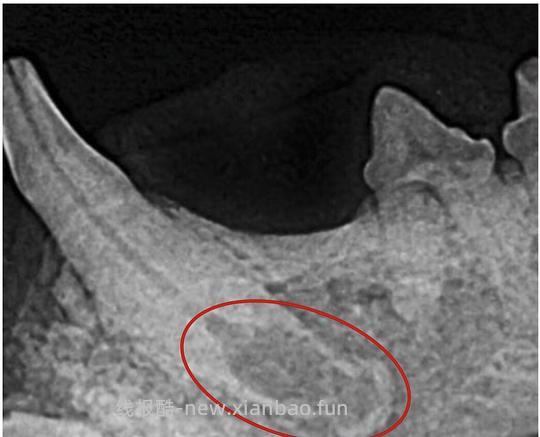

内吸收由慢性不可逆转的牙髓炎和牙髓腔内小区域的坏死引起,通常偶见于猫。受内吸收影响的牙齿可能因发炎的牙髓呈现轻微的粉色。在影像学上,内吸收表现为与牙髓相邻的离散椭圆形扩大,一般位于根管顶端的1/3处,如图所示,可通过拔牙或根管治疗阻止吸收继续发生[1]。

![【科普】[养猫笔记05-医疗] 猫牙破齿细胞吸收性损伤(FORL)— 猫第二大常见疾病 - 线报酷 【科普】[养猫笔记05-医疗] 猫牙破齿细胞吸收性损伤(FORL)— 猫第二大常见疾病 - 线报酷](https://new.xianbao.fun/plus/api/image.php?imgurl=https://img2.doubanio.com/view/group_topic/m/public/p645120142.jpg)

图7 犬齿内吸收[1]